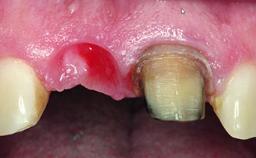

A 30-year-old patient presented at our clinic with a chief complaint of pain in her endodontically treated right maxillary central incisor (tooth 11) with a post-and-core and a fixed single crown. She had a very high lip line, a medium to thin soft-tissue phenotype, and a medium scalloped gingival contour. She also had high esthetic expectations because of her young age and beautiful smile. However, her expectations were realistic and she understood the risks of the treatment. At the initial clinical examination there was a slight mobility of tooth 11; no fistula was observed. The patient also had a single crown on the adjacent tooth 21. Both restorations were old and esthetically deficient. A digital periapical radiograph showed a very small periapical radiolucency, a thick intraradicular post, and no separation between root fragments.